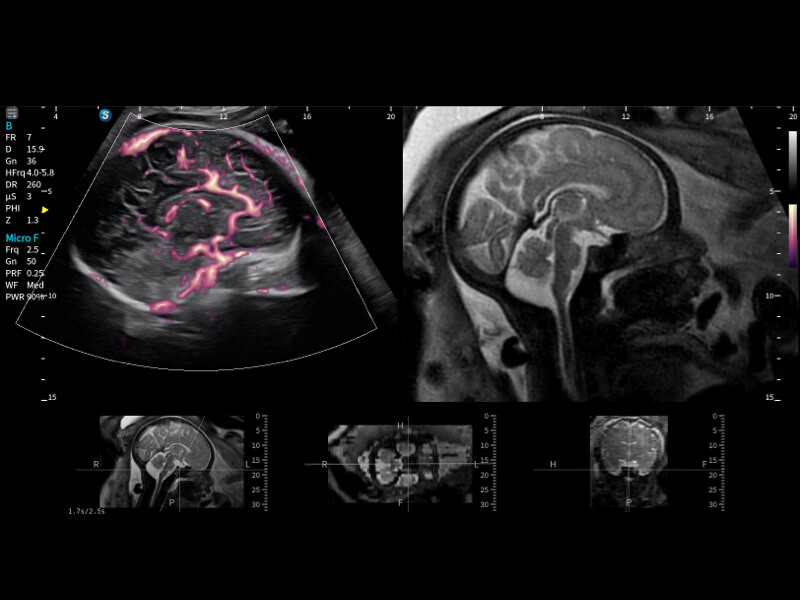

細(xì)微血流 纖毫畢現(xiàn)

豐富的血流動(dòng)力學(xué)檢測(cè)技術(shù),可在不同醫(yī)療場(chǎng)景中高效捕捉血流信號(hào),助力臨床診療。

• Micro F+顯微血流成像

通過創(chuàng)新的Matrix E自適應(yīng)濾波算法,能有效濾除軟組織和噪聲信號(hào),最大限度保留超低速微細(xì)血流的信號(hào);結(jié)合超長時(shí)間域算法,極大提升細(xì)微血流的敏感性和空間分辨率,更真實(shí)的反應(yīng)組織、包塊的血流灌注情況。

胎兒顱腦融合